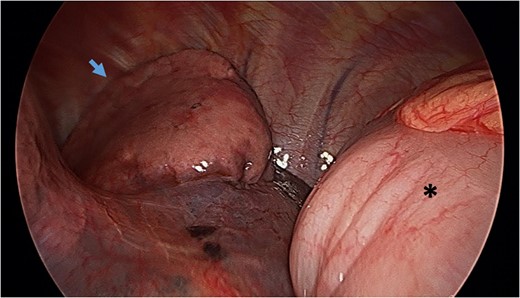

Video-assisted thoracoscopy (VAT) demonstrating a loop of transverse colon in the left hemithorax. Black asterisk (*) indicates a loop of transverse colon. Blue arrow indicates deflated left lung.